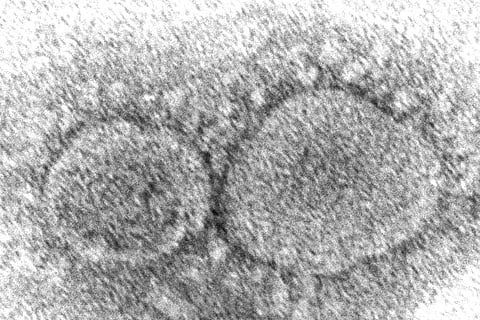

இந்நிலையில் ஒமைரான் கரோனா தொற்றால் பாதிக்கப்படும் நாடுகளின் எண்ணிக்கை 59ஆக உயர்ந்துள்ளது. இதுதொடர்பாக செய்தியாளர்களை சந்தித்த மத்திய சுகாதாரத்துறை அதிகாரிகள் நாட்டின் கரோனா தொற்று பரவல் சூழலை விளக்கினர்.

அப்போது உலகின் 59 நாடுகளில் ஒமைக்ரான் தொற்று பரவல் கண்டறியப்பட்டுள்ளதாகத் தெரிவித்த மத்திய சுகாதாரத்துறை உலகம் முழுவதும் இதுவரை 2,936 பேருக்கு ஒமைக்ரான் கரோனா தொற்று இருப்பது உறுதிசெய்யப்பட்டுள்ளதைக் குறிப்பிட்டு பேசினார்.

சர்வதேச நாடுகளுடன் ஒப்பிடுகையில் பிரிட்டனில் அதிகபட்சமாக 817 பேரும், டென்மார்க்கில் 796 பேரும் தென்னாப்பிரிக்காவில் 431 பேரும் ஒமைக்ரான் கரோனா தொற்றால் பாதிக்கப்பட்டுள்ளனர்.